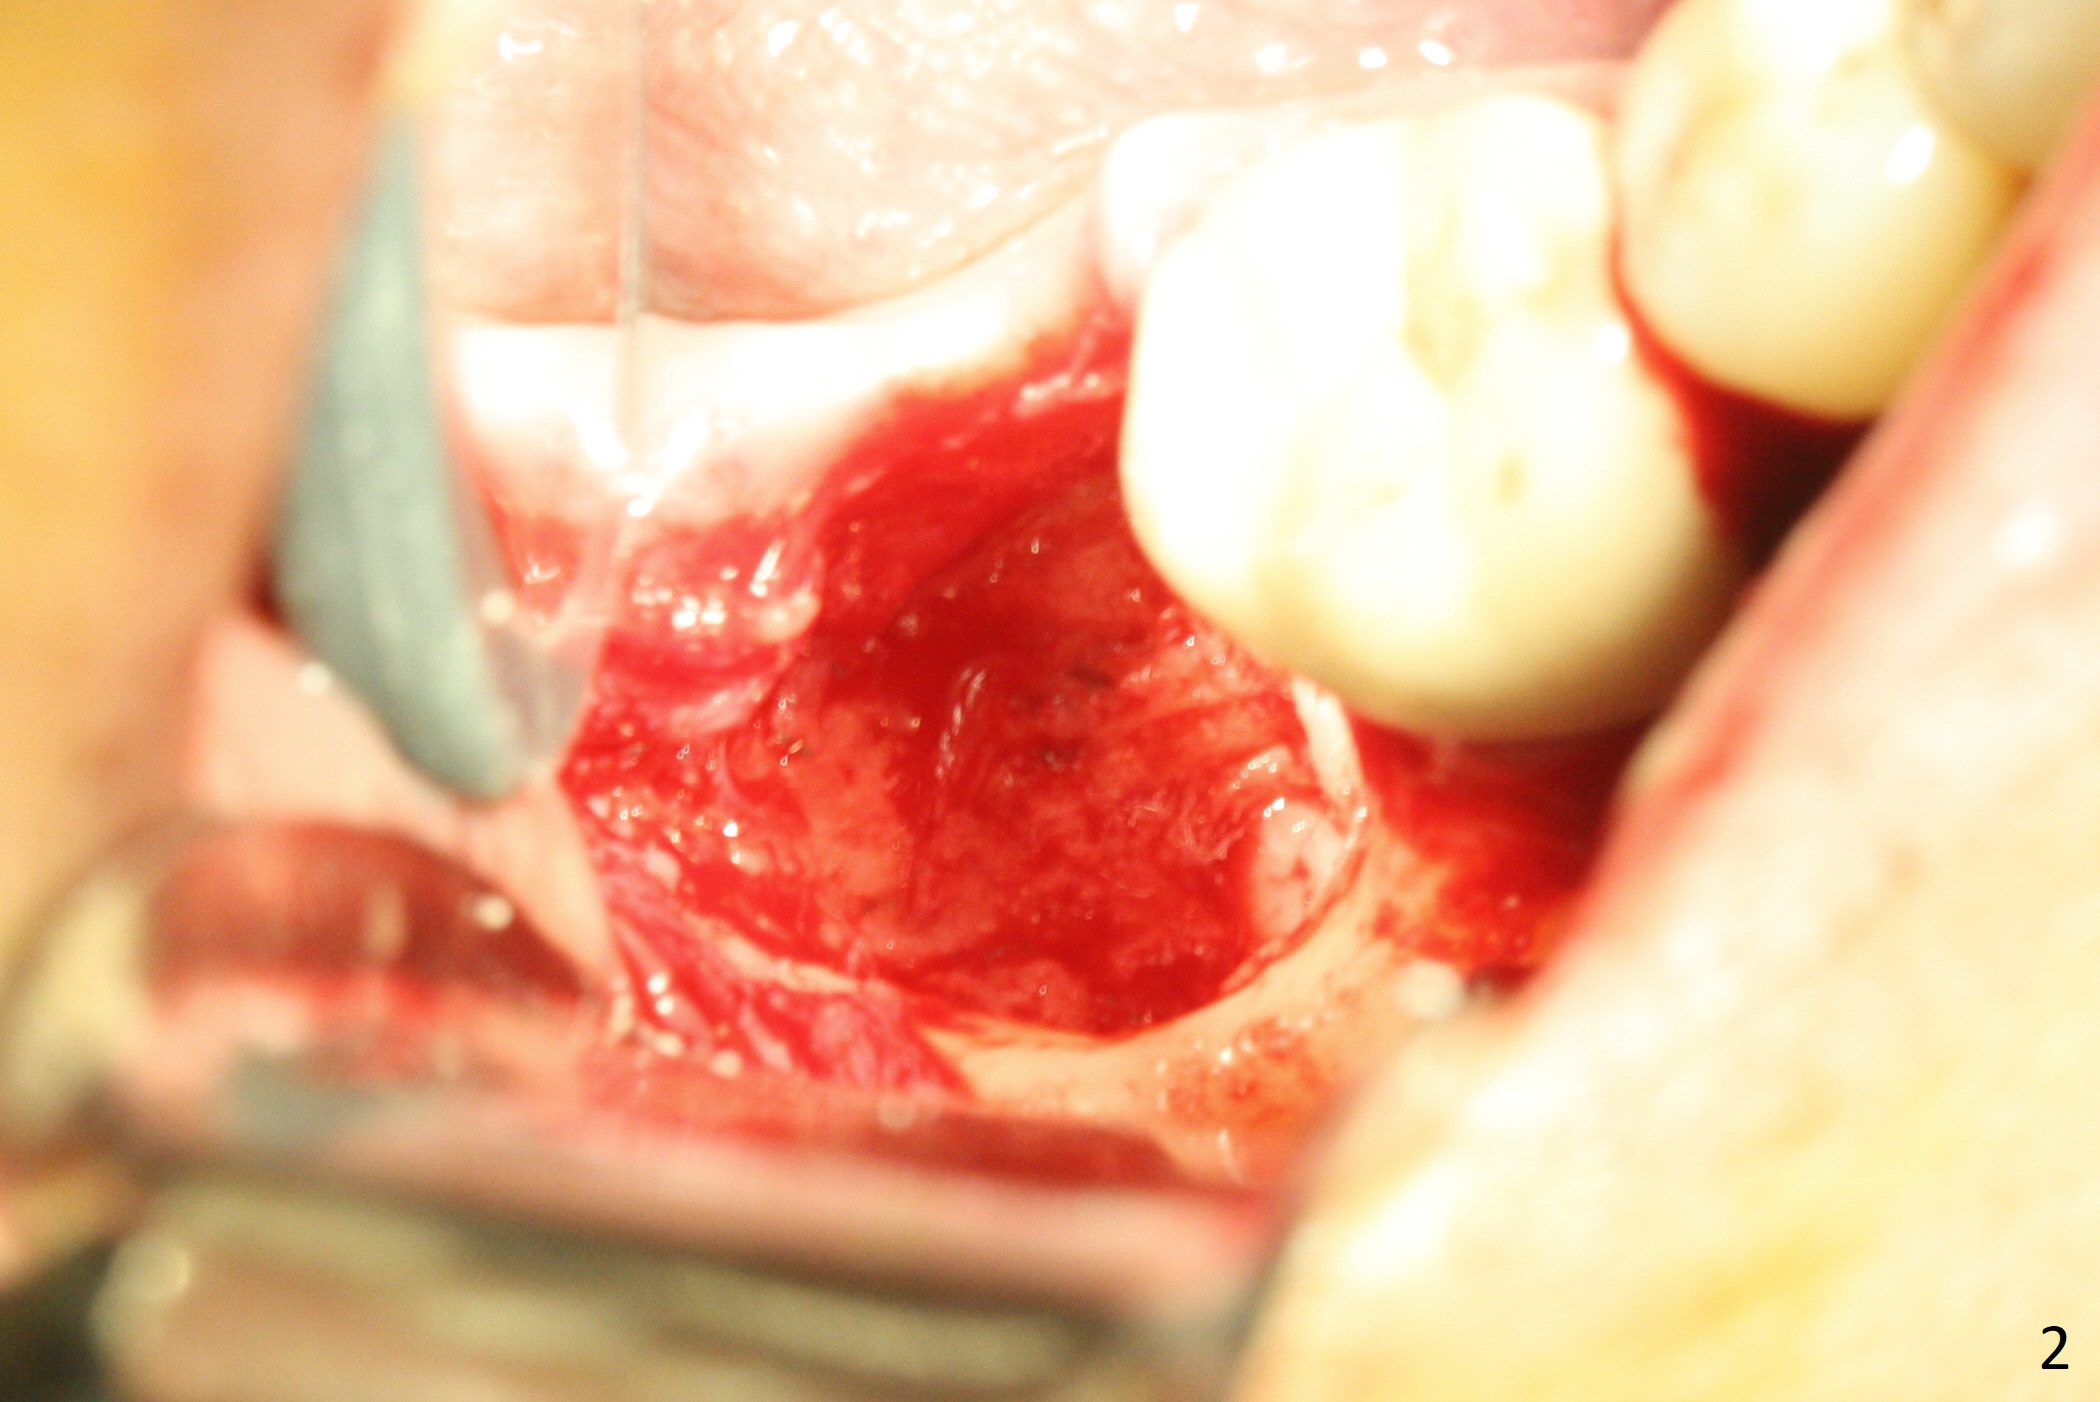

There is a mesiobuccal fistula at #31 with periimplantitis (Fig.1 ^). The bone loss is severe before and after implant removal (Fig.2). It is impossible to place bone-level implant in the original osteotomy due to insufficient bone height. There is pain when a new osteotomy is being initiated in the mesial slope. Following placement of Vera Graft (Fig.3), collagen plug and 6-month resorbable membrane, the wound is closed with suture (mild tension). Postop, there is oozing. Periodontal dressing should have been applied. If the ridge can be preserved in 4-6 months, a 11 mm long implant (Fig.4 green line with 4 mm of the native bone) can be placed with 1.9 mm clearance (red dashed line: the superior border of the Inferior Alveolar Canal); the abutment is estimated to have 4 mm cuff (pink). The socket appears to be healing 8 days postop (Fig.5). The ridge remains wide 5 months post implant removal, although the bone density is low (Fig.6,7 (still ~ 1000 units). It seems that a 5x11.5 mm implant could be placed in the mesiobuccal aspect of the bony defect (Fig.8). For better occlusion, the implant should be shorter (5x8.5 mm) after discussion with the guide lab (Fig.9). Make sure that the most coronal thread is buried by the bone graft, i.e., underneath the crest(>).